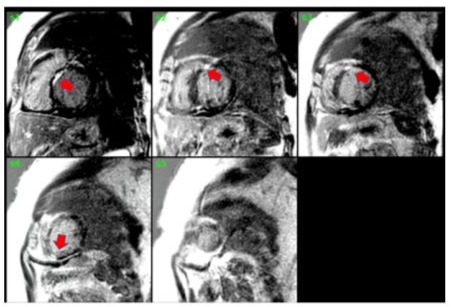

A 56-year-old male with pre-existing diabetes, dyslipidemia, hypertension, and heart failure with mildly reduced ejection fraction was diagnosed in 2022 when the patient presented with symptoms of new-onset heart failure, including shortness of breath upon exertion, orthopnoea, and generalized body swelling. Admitted and worked up at that time for new-onset heart failure. The workup included echocardiography, which was reported with regional wall motion abnormalities in the septal, anterior, and apical akinesis, with a moderately reduced Ejection fraction of 40-45 %. The patient’s ECG at that time showed normal sinus rhythm with a PR interval of 300 (Figure 1). Cardiac catheterization showed mild, nonobstructive coronaries; therefore, the patient was labelled as having non-ischemic cardiomyopathy. Advanced cardiac imaging showed a mildly dilated left ventricle with moderate systolic dysfunction, LVEF = 41%. Delayed patchy myocardial enhancement imaging showed the presence of 25-50% sub-endomyocardial enhancement in the anterior, anteroseptal, and apex, strongly suggesting cardiac sarcoidosis (Figure 2). The patient was discharged on anti-failure medication, including loop diuretics and a maintenance dose of 2.5 bisoprolol. However, in June 2024, the patient was presented to our emergency department with the main complaint of lower limb swelling. The patient denied any symptoms of shortness of breath, syncope, dizziness, or fatigue. Upon an emergency workup, the patient’s ECG showed a new-onset 3rd-degree heart block with atrial flutter (Figure 3). The patient’s vitals were remarkable, with a heart rate of 38 and blood pressure of 70/50. He was started on dopamine infusion and bedside transcutaneous pacing. His bisoprolol was held, and the initial laboratory investigation was sent with no significant abnormalities. He was admitted for further workup and management. The patient was urgently pushed to the Cath lab, where a temporary pacemaker was inserted. The patient’s ECG strip showed continuous pacing, proving the patient was pace-dependent. A Repeated Echocardiograph done in July 2024 was significant for a further drop in EF, 35-40%, and mild to moderate valvular aortic stenosis. The patient was shifted to the electrophysiology lab afterward, where he underwent successful insertion of a CRT-D to the mid-posterior coronary sinus, extending to the lateral wall, programmed to DDD-adaptive at 60 bpm. The patient was shifted to the floor in stable condition with a biventricular-paced rhythm. Given his CHAD Vasc score of 2, he was started on appropriate anticoagulation. An extensive workup to investigate the underlying cause of the coexistence of these contradictory electrical phenomena included an amyloidosis workup, which came back negative for urine light chains and immunofixation with unremarkable serum protein electrophoresis. Infectious causes, including COVID-19, were negative. The patient’s chest CT showed bilateral hilar lymphadenopathy. In the light of excluding other medical causes, the patient was presumed to have sarcoidosis, given his clinical scenario and sarcoidosis diagnosis score of 5. Thus, the pulmonology team was involved, and a bronchial biopsy was done, which came back negative for non-caseating granuloma. A whole-body PET scan showed no evidence of active inflammation. One week following device implantation, the patient underwent synchronized cardioversion with successful restoration of sinus rhythm.

Figure 2: Delayed myocardial enhancement imaging showed the presence of 25-50% sub-endomyocardial patchy enhancement in the anterior, anteroseptal, and apex sarcoidosis.